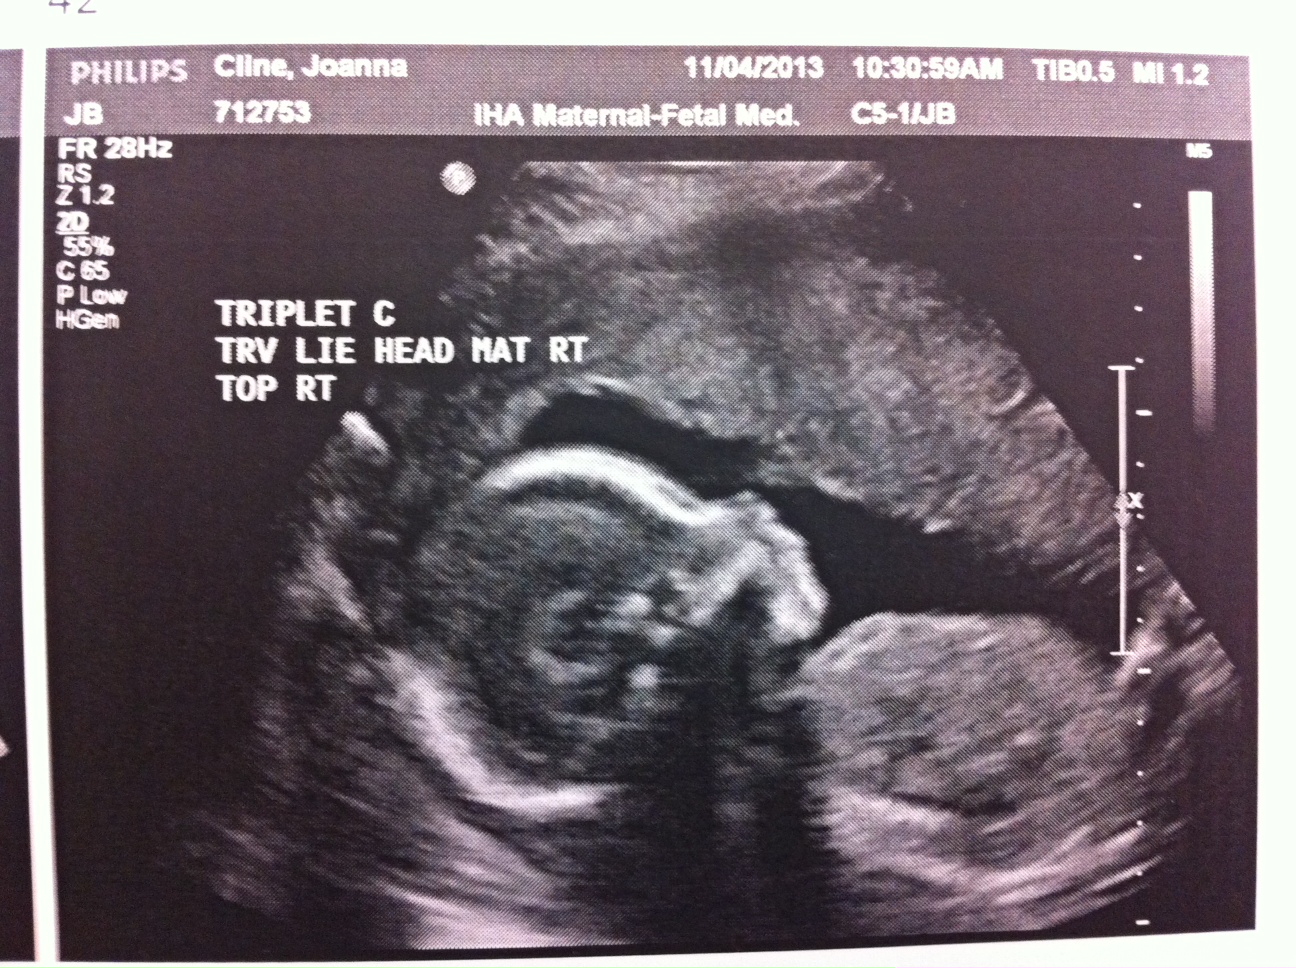

Obviously 24 weeks is still very early (and risky) and we don’t want these babies born yet but it’s still a great checkpoint in my pregnancy. Fortunately, everything looked fantastic at my appointment today. A, B and C looked great and my body is currently a fortress sealing them in where they belong.

Two photos are attached. This week, only A wanted to show his face. And I attached a V Day photo of me. I’m really not sure how my belly is going to get bigger but I’m told it will happen!